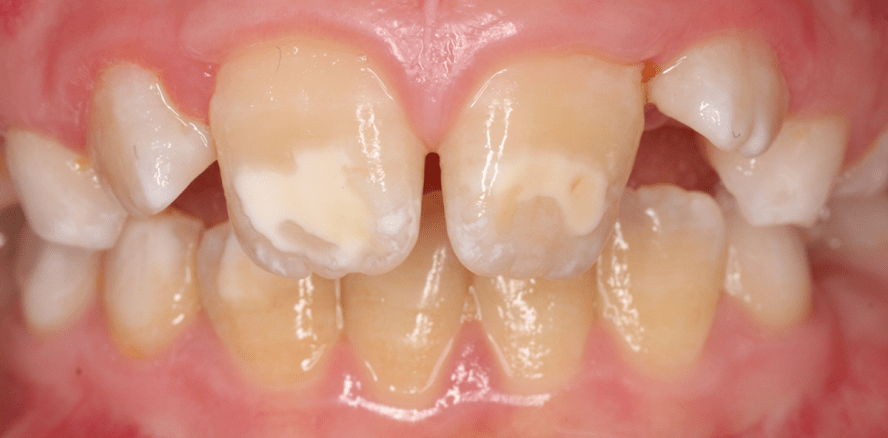

Bei der MIH handelt es sich um eine systemisch bedingte Hypomineralisation von ein bis vier bleibenden ersten Molaren, die häufig mit der Fehlstrukturierung der Inzisiven assoziiert ist (Abb. 1 und 2).1 Je mehr Molaren betroffen sind, umso größer ist die Gefahr, dass auch die oberen Inzisiven Defekte aufweisen. Der Begriff der Molaren-Inzisiven-Hypomineralisation wird seit dem Kongress der European Academy of Paediatric Dentistry (EAPD)1 im Jahre 2001 verwendet. Zuvor wurden diese Störungen der Zahnhartsubstanz als nicht endemische Schmelzflecken, idiopathische Schmelzhypomineralisation der ersten Molaren,2 Cheese molars3 oder nicht fluoridbedingte Hypomineralisationen der ersten Molaren4 bezeichnet. Die Molaren-Inzisiven-Hypomineralisation tritt bei Kindern weltweit auf, wobei die Angaben in der Literatur zur Prävalenz schwanken. Berichtet wird von Häufigkeiten zwischen 3,6 Prozent und 25 Prozent.5 Das Auftreten wird in den nordischen Ländern mit 10 bis 19 Prozent angegeben. In Deutschland leiden im Durchschnitt wahrscheinlich etwa 4 bis 14 von 100 Kindern an MIH.2, 6–8

Betroffen sind klassischer Weise die ersten bleibenden Molaren und die Inzisiven, wobei innerhalb einer Dentition beträchtliche Unterschiede bestehen. Meist sind die Sechsjahrmolaren häufiger und ausgeprägter betroffen als die Schneidezähne. Die Oberkieferschneidezähne sind wiederum eher befallen als die unteren.4 Sind jedoch die Unterkieferfrontzähne betroffen, so kann man davon ausgehen, dass sowohl die Oberkieferschneidezähne als auch die Molaren Hypomineralisationen aufweisen.2 Dabei können lediglich einzelne Höcker oder aber die gesamte Glattfläche bzw. das Fissurenrelief bis hin nach zervikal betroffen sein.2 Die fehlstrukturierten Zähne zeichnen sich klinisch durch eine Veränderung in der Transluzenz des Schmelzes aus. Die Opazitäten können in ihrer Farbe weiß, creme, gelb oder braun sein. Geringgradig veränderte Zähne zeigen eher weiß-gelbliche oder gelb-braune, unregelmäßige Verfärbungen im Bereich der Kauflächen und/oder Höcker, schwere Hypomioneralisationsformen weisen dagegen abgesplitterte oder fehlende Schmelz- und/oder Dentinareale unterschiedlichen Ausmaßes auf.2 Je dunkler die Farbe, umso poröser ist der Zahnschmelz und umso höher ist die Gefahr des posteruptiven Substanzverlustes (meist an den Zahnhöckern) mit Dentinexposition. Die hypomineralisierten Zähne weisen im Vergleich zu nicht erkrankten Zähnen strukturelle Defizite auf. Sie sind nicht nur optisch verändert, sondern der befallene Schmelz unterscheidet sich auch durch geringere Härte, niedrigeren Mineralgehalt und erhöhte Porosität. Hierdurch wird die mechanische Belastbarkeit herabgesetzt. In der Folge platzt der Schmelz beim Kauen ab und scheint geradezu wegzubrechen.5, 7,11 Röntgenologisch ist hypomineralisierter Schmelz dem Dentin sehr ähnlich. Mikroskopisch liegen Unregelmäßigkeiten der Schmelzstruktur in Form von veränderter Verdichtung und Ausrichtung der Mikrokristallite vor. Zu ergänzen ist, dass vereinzelt als MIH beschriebene Defekte auch an anderen Zähnen der bleibenden Dentition (7er, 5er, 3er) beobachtet worden sind. Des Weiteren finden sich vermehrt auch Hypomineralisationen an den zweiten Milchmolaren und den Milcheckzähnen. Auch hier sind die Ursachen noch unklar. Klinisch können Hypomineralisationen an den Sechsjahrmolaren in drei Schweregrade von 1 (leicht) bis 3 (schwer) eingeteilt werden (nach Wetzel und Reckel).15 Dabei weisen Molaren mit Schweregrad 1 einzelne weiß-cremige abgegrenzte Opazitäten im Bereich der Kaufläche und/oder der Höcker/des oberen Kronendrittels ohne Substanzverlust auf (Abb. 3). Bei Schweregrad 2 erfassen die Opazitäten dann fast alle Höcker und das obere Kronendrittel bei geringem Substanzverlust (Abb. 4). Schweregrad 3 ist durch großflächige, gelb-braune Verfärbungen mit Defekten der Kronenmorphologie aufgrund ausgeprägter Schmelzverluste gekennzeichnet (Abb. 5). Alle diese Schweregrade können mit oder ohne Beteiligung der Schneidezähne auftreten.6 Aktuelle klinische Kriterien zur Erfassung der hypomineralisierten Zähne liegen von der EAPD vor.16 Sie beinhaltet eine Klassifikation in 3 Graden und das Fehlen von Index-Zähnen (Tab. 1).